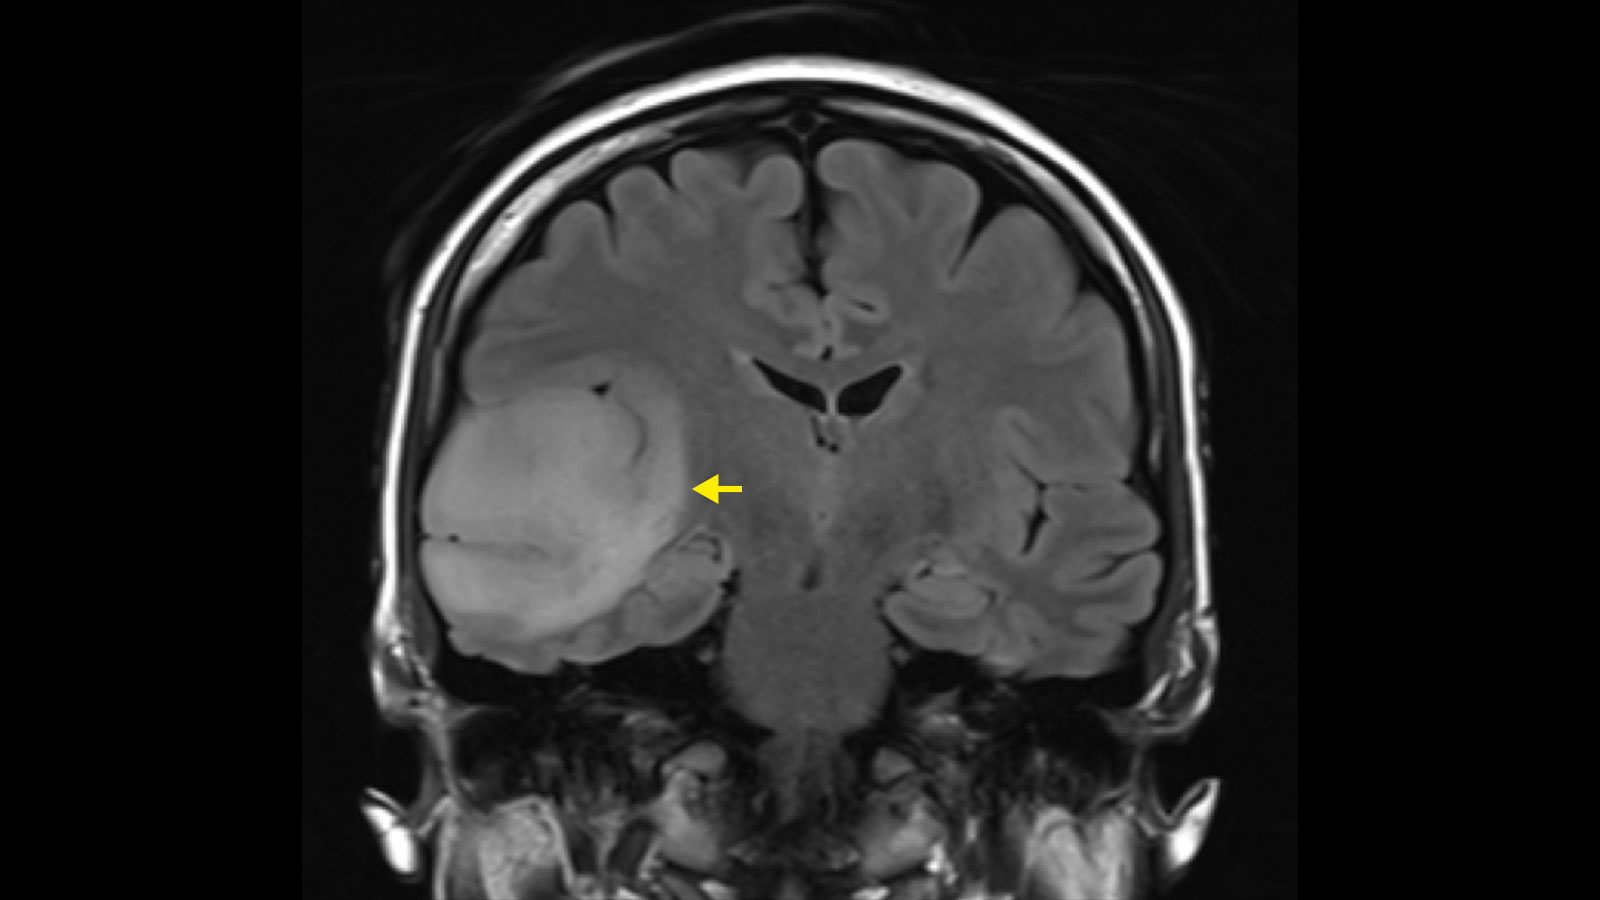

Ilustrační foto.

Zdroj: Universitätsklinik für Neurochirurgie, Inselspital Bern